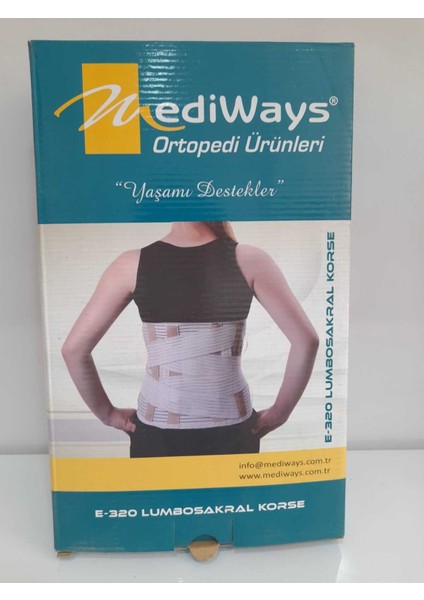

About The Perfect Lumbosakral Destek Korsesi 26 Cm, Rahat ve Güvenli Kullanım Sağlar.

About The Perfect Lumbosakral Destek Korsesi 26 Cm, Rahat ve Güvenli Kullanım Sağlar.

Süpermarket/Sağlık/Medikal Ekipman/Ortopedi Ürünleri/Medikal KorseGörsel